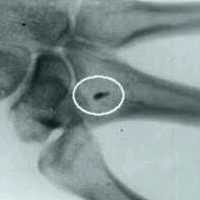

Hasta el momento de conocerlo, cuenta Jaime Maussan, que él no recordaba absolutamente nada de los ocurrido, y le fue diagnosticada ," perdida de tiempo", alrededor de 40 años después, concurre al médico y le hacen estudios por un problema que tiene en una mano, descubren en una radiografía que tiene incrustado un trozo de metal, el ignoraba ésto y se da cuenta de que tiene un implante, pero desconocía el tema; hasta que casi por casualidad ve en la tele un programa de Roger Leir, y accede a que el implante sea extraído.

Estas son algunas de las imágenes , de objetos extraidos del cuerpo de personas abducidas, y tamben de placas radiográficas sacadas antes de la cirugía.